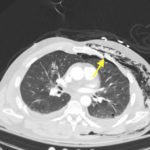

Plain film anteroposterior (AP) radiography of the chest shows left-sided subcutaneous emphysema (red arrow) with overlapping muscle striations of the pectoralis major (green arrow). After chest tube placement (blue arrow), AP chest radiography shows persistent left-sided subcutaneous emphysema (red arrow). CT of the chest shows pneumomediastinum (blue arrow), left apical pneumothorax (pink arrow), and subcutaneous emphysema (red arrow) at the level of T2. At the level of T6, rib fractures can be visualized on the CT (yellow arrow). At the level of T8, left sided pneumothorax is also seen (pink arrow) as the absence of lung tissue on CT.

In this patient, given the findings of multiple bilateral rib fractures, bilateral hemothorax/pneumothorax and multiple spine fractures, bilateral chest tubes were placed which had immediate output. The patient was admitted to surgical intensive care unit for chest tube management, pulmonary hygiene and further management of his other injuries.